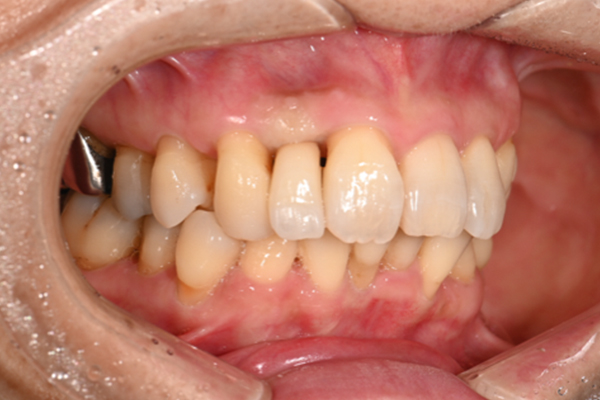

| 主訴 | 歯がグラグラして噛めない |

|---|---|

| 治療内容 | 上顎に対するインプラント治療 |

| 治療期間 | 1日 |

| 治療費 | 204万6千円 |

| 治療 リスク | 最終的な歯が入るまでは仮歯になります。 |